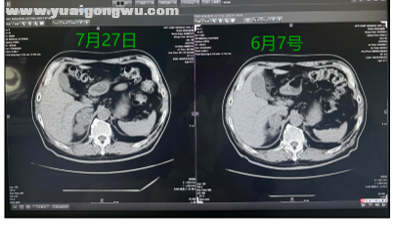

关于腹部右侧肾上腺的影像,仅提供了6 月7日和7月27日的两张图,且层面可能不完全一致。从这两张图来看,7月27日的病灶(呈葫芦形)较6月7日有所增大,提示可能进展。以上为影像方面的评判内容。

王群慧教授 由于影像截图来自云胶片,有时定位可能不够精准,但依据现有报告,肺部整体变化处于稳定状态。6月与7月的腹部影像报告显示,病灶最长径无变化,仅短径存在变化。该患者接受了新辅助治疗及手术,术前根据PET-CT所示的高代谢淋巴结位置判断,分期接近Ⅲb期。对于此类患者,通常会如何处理?其纵隔内右上气管旁的淋巴结位置,大致接近2R及4R区。

张旭教授 在患者全身控制相对稳定的前提下,若发现肾上腺存在局部进展且病理已明确,建议及时对肾上腺转移灶进行局部放疗。这种治疗手段应用广泛且技术成熟。对比患者近期肾上腺的两次影像,病灶在影像上呈现变大、变饱满的状态。在确保肝功能不受损的情况下,可加大放疗的单次剂量、缩短疗程,通过较强的局部姑息放疗,实现对该病灶的良好控制。

王群慧教授 患者经新辅助治疗后出现转移,经化疗联合免疫治疗后,目前病情较为稳定,肺上的病灶处于稳定状态。腹部右侧肾上腺的病灶,从报告来看,长径无大小变化,但短径较之前有所增大,从临床肿瘤进展判断仍属稳定。对于前期出现的右侧肾上腺转移,可采用放疗进行有效的姑息性治疗。